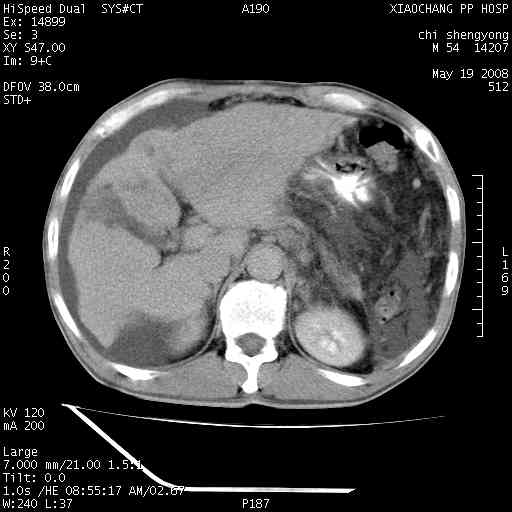

以下是引用zjzjr在2008-5-21 10:52:00的发言:[br]肝左叶巨块型肝癌伴门静脉左支瘤栓形成.肝硬化、腹水,胃底静脉曲张,脾术后改变。

以下是引用随光逐影在2008-5-21 16:20:00的发言:[br]1)肝左叶肝癌伴门静脉左支瘤栓形成,腹膜后淋巴结转移。2)肝硬化、腹水、胃底静脉曲张。3)胆囊炎。4)脾脏缺如,为切除术后所致。